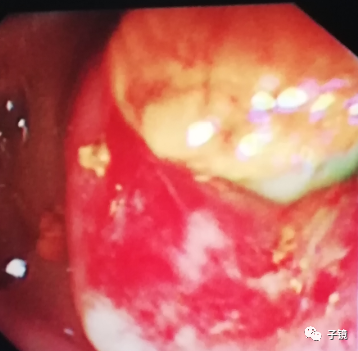

因为镜身固定困难,行乳头切开时调不到最佳的位置,所以进直径10mm球囊扩张导管扩张乳头,扩开后乳头有渗血。

取石球囊怎么取石“ERCP球囊取石细节讨论”学习笔记_https://www.jmylbn.com_新闻资讯_第6张